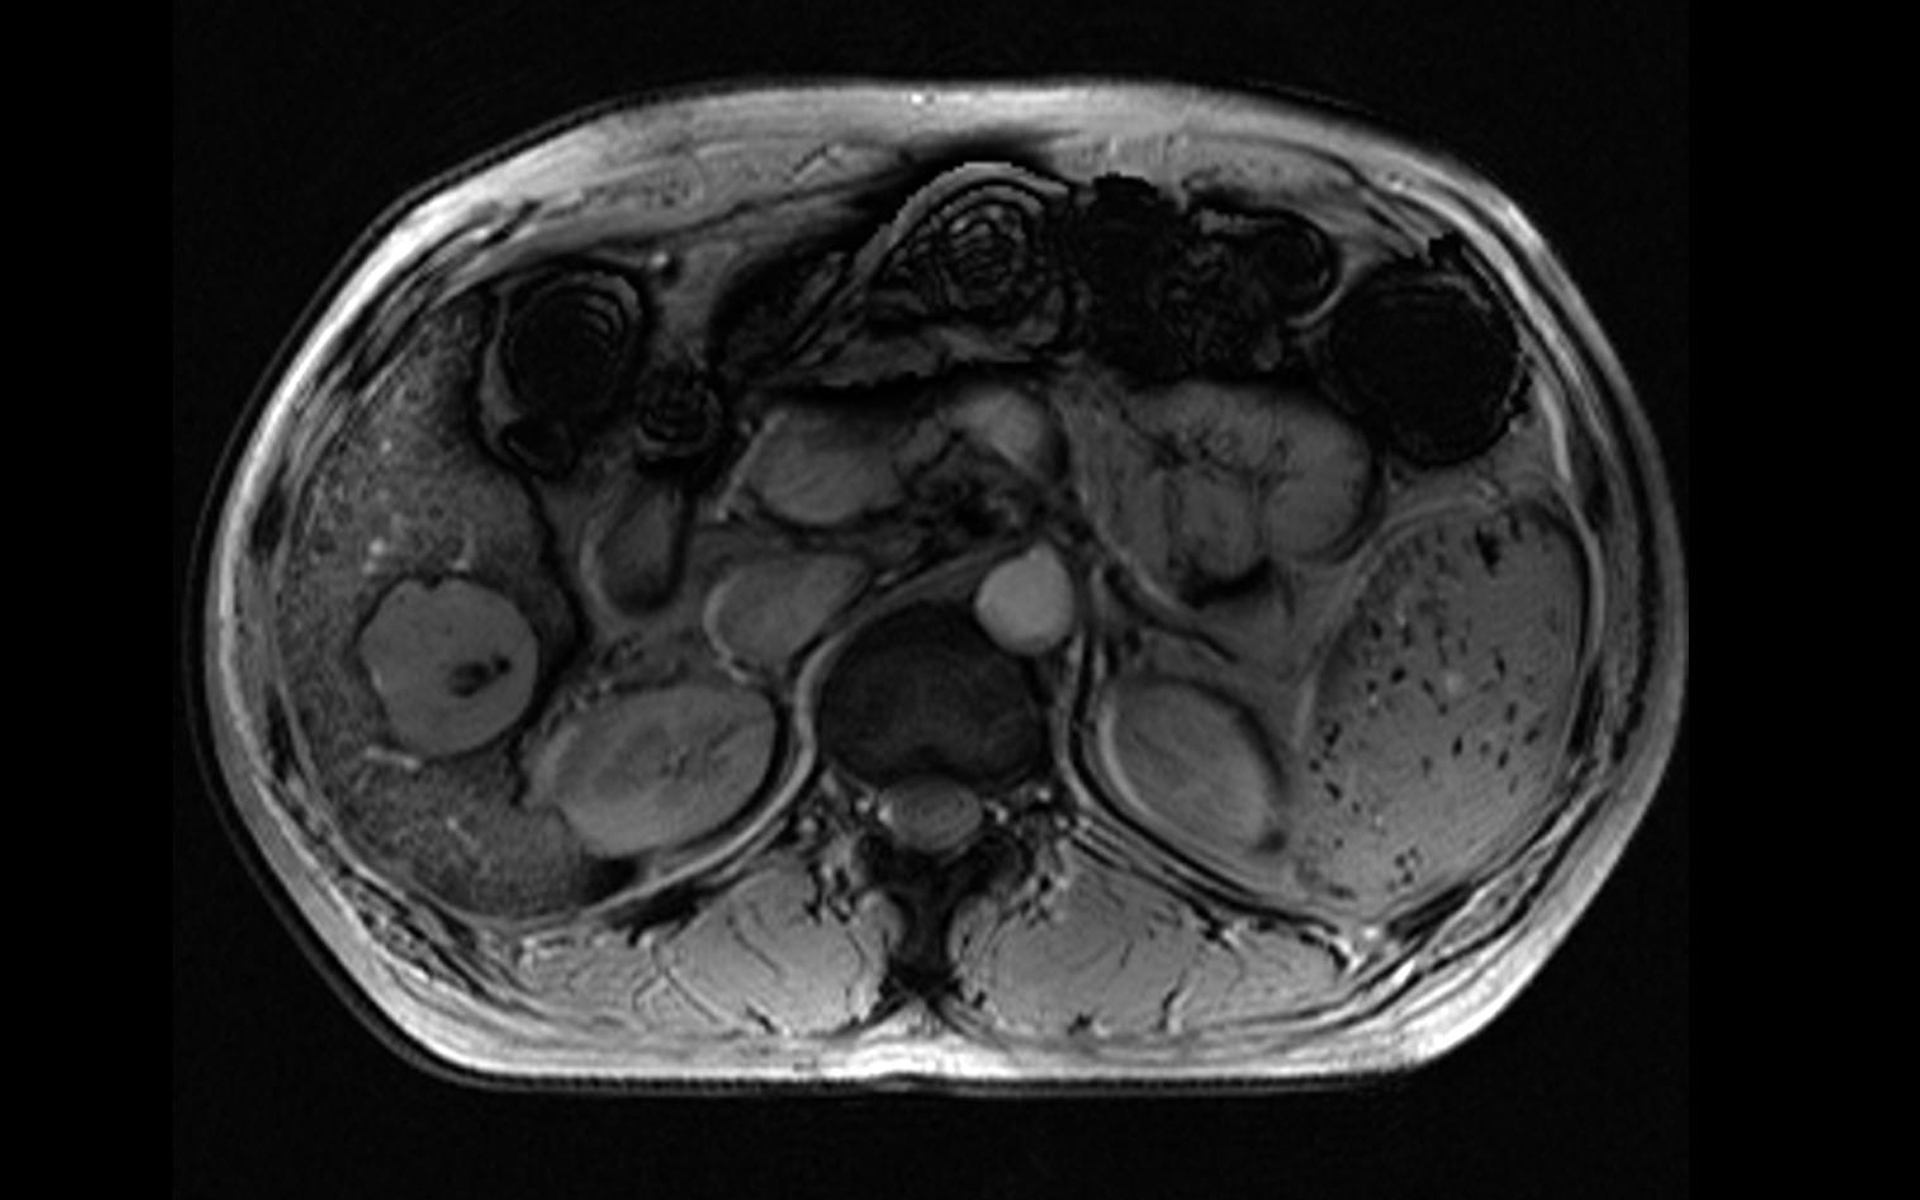

高效高收益

大幅提升患者流通量。